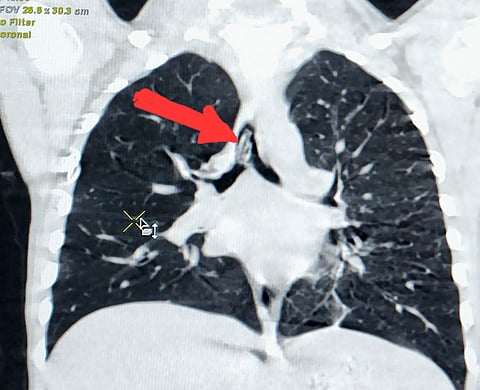

ووفقًا لما ذكرته صحة الطائف لـ"سبق"؛ فقد كان الطفل الذي يبلغ من العمر 3 سنوات، قد حضر مع ذويه إلى طوارئ المجمع، يعاني من اختناق شديد مصحوبًا بصوت تصفير مع كل تنفس للطفل، وبعد الكشف عليه اتضح وجود جسم غريب، سقط في مجرى الهواء.

ومع انتهاء الكشف، قرر فريق طبي مكون من أطباء جراحة الصدر وأطباء التخدير، على الفور، إجراء عملية منظار عاجلة لاستخراج الجسم؛ حيث استغرق الإجراء الطبي 20 دقيقة، وتبين بعد استخراج الجسم أنها صافرة ابتلعها الطفل أثناء اللعب.